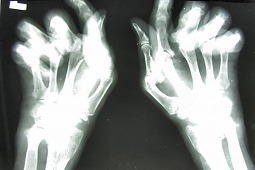

Polskie Towarzystwo Reumatologiczne: nie manipulujcie przy programach

Chodzi o programy lekowe. Konkretnie o program dotyczący RZS. Ministerswo Zdrowia chce zaostrzyć kryteria dostępu do programów. Protestuje przeciw temu PolskieTowarzystwo Reumetologiczne.